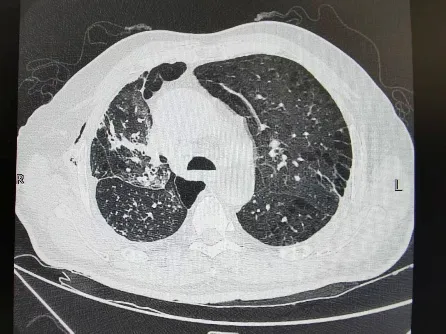

出院前肺CT

术后第三天,在多学科团队的共同照料下,刘先生即可下床活动,胸闷、气短等症状完全消失。复查显示,双侧肺组织复张良好,肺功能指标逐步恢复正常。出院时,普外科、呼吸科与中医团队共同为他制定了长期康复方案,指导他通过戒烟、饮食调理、中药巩固与呼吸训练结合,预防肺部疾病复发。